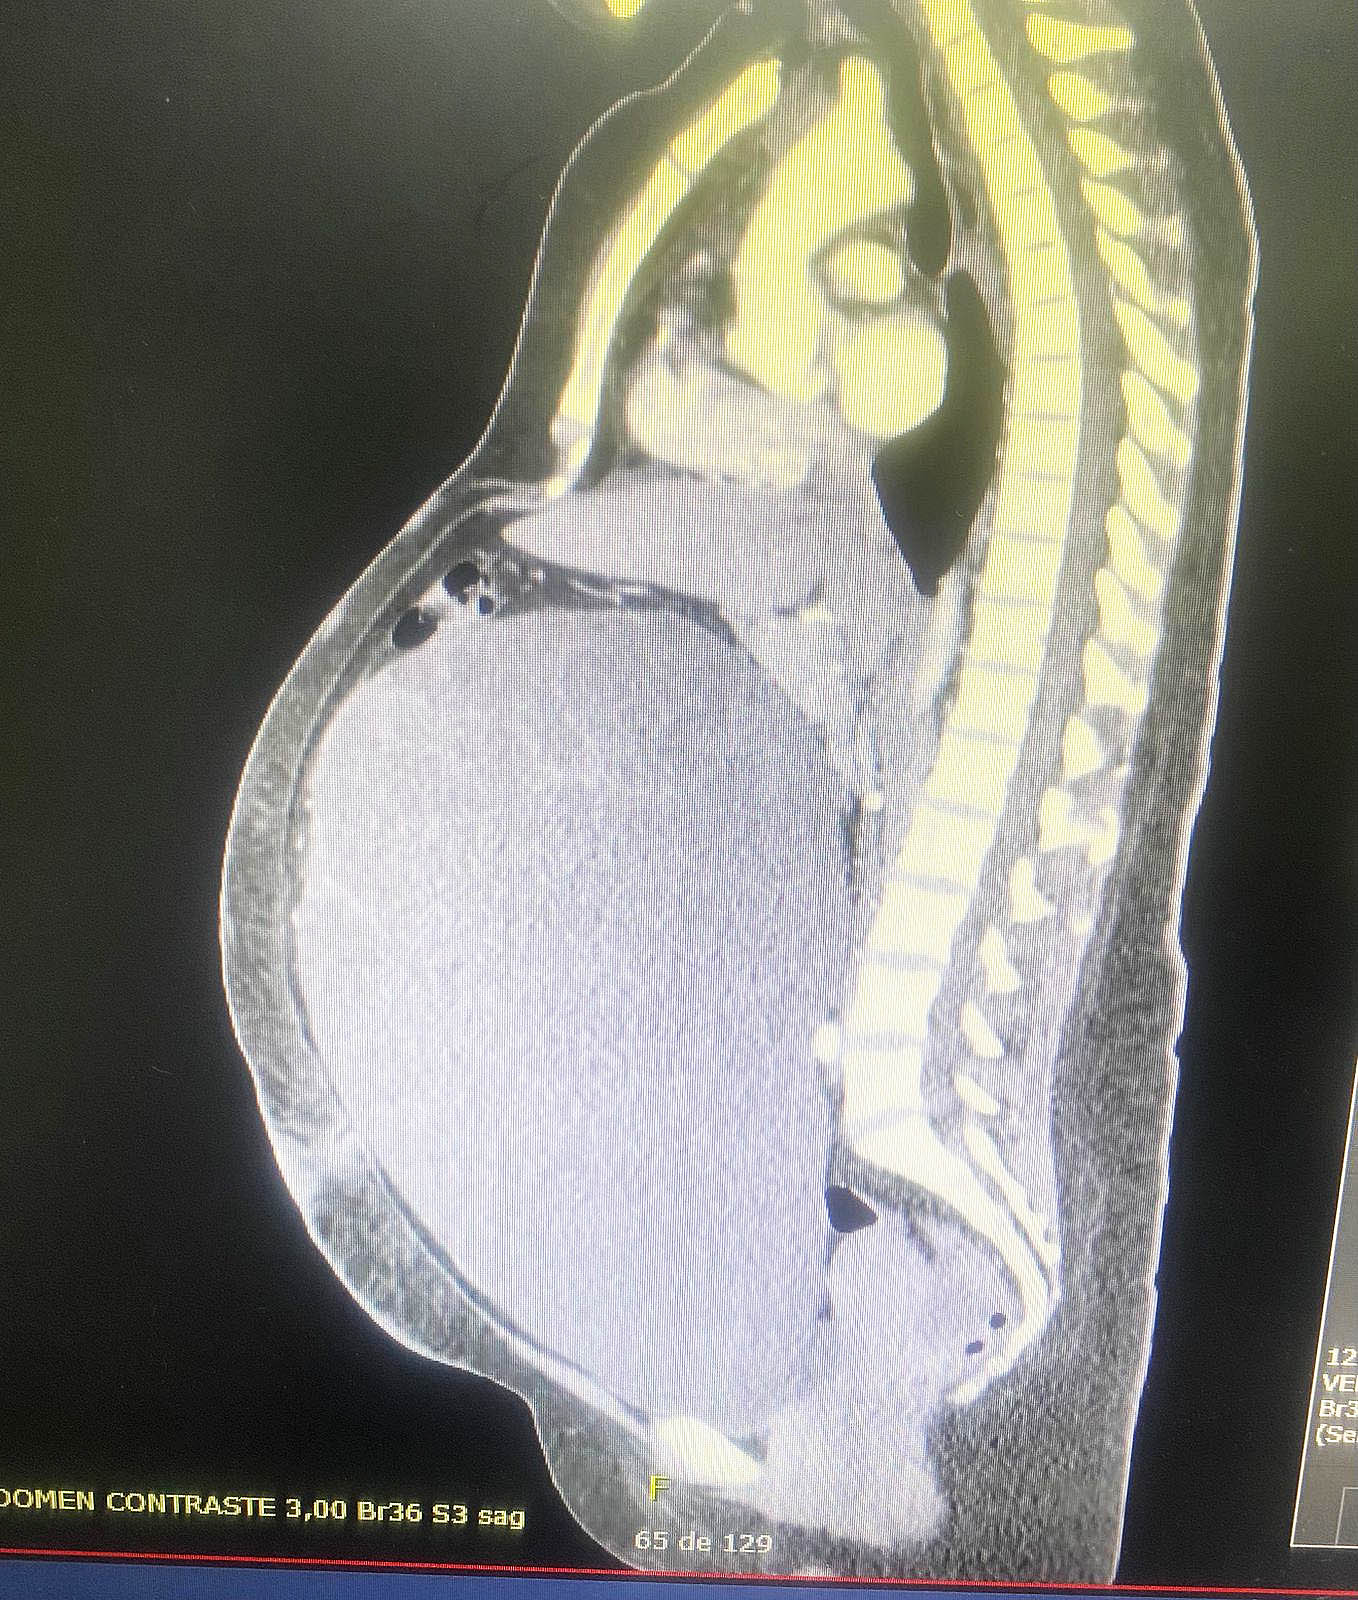

En horas de la mañana de este lunes 16 de marzo, una paciente de 34 años con antecedente de crecimiento abdominal progresivo de larga data fue atendida en el Servicio de Ginecología del Hospital Central, donde quedó internada para la realización de estudios diagnósticos completos. Tras una evaluación integral que incluyó análisis laboratoriales, estudios de imágenes y la valoración por diferentes especialistas del hospital, se llegó al diagnóstico de un tumor abdominal de origen ginecológico.

Tras la intervención, se constató que el tumor presentaba dimensiones aproximadas de 36 x 27,5 x 19 centímetros y un peso superior a los 10 kilogramos, lo que evidencia la magnitud de la patología tratada.